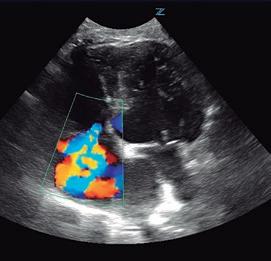

Bloqueantes de canales del calcio Hidralazina, nitratos e IECA